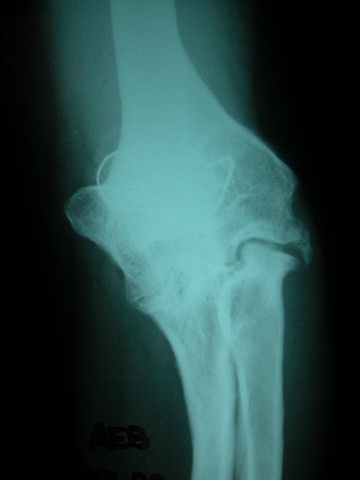

ACT artrosis muy severa de codo.